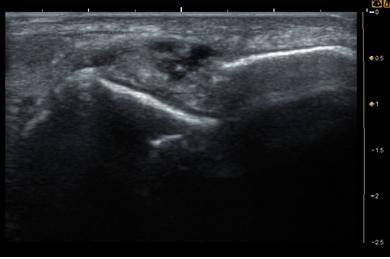

![발목인대손상 초음파소견. [사진 유재욱]](https://img4.daumcdn.net/thumb/R658x0.q70/?fname=https://t1.daumcdn.net/news/201806/21/joongang/20180621172508470niss.jpg)

"발목인대가 다쳐있는데다 쉬어줘야 하는데 계속 무리해서 써서 그래요. 좀 어떻게 변했는지 초음파로 한번 봅시다. 어휴, 이것봐. 발목인대가 파열되고 염증이 생겼잖아. 이러면 발목이 아플 뿐만 아니라, 발목의 안정성이 떨어져서 발목이 흔들리게 되거든. 이렇게 발목 불안정성이 계속되면 나중에는 발목관절까지도 상할 수가 있어요. 발목관절까지 안 좋아지면 수술을 해야 할 정도로 진행할 수도 있으니 지금 정신 차리고 관리를 잘해야 해요."